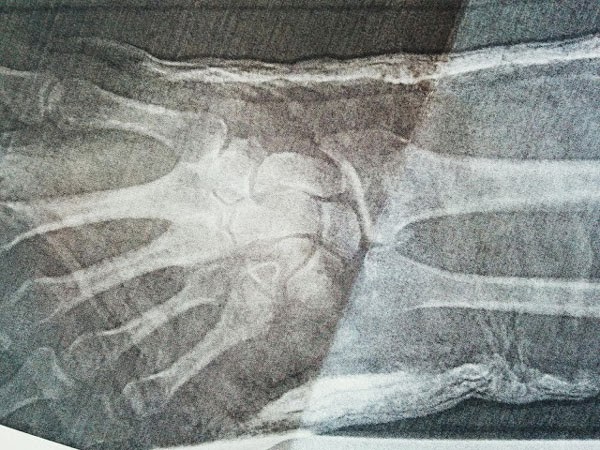

Non-eventful drive to the North Shore Hospital to be assessed, x-rayed and diagnosed... impacted intra-articular fracture of left distal radius with ulnar styloid fracture. In layman's terms my ulnar and radius had tried to force themselves under my wrist.... fuck!

The consultant and orthopaedic team decided that a Biers Block procedure was the best option. That is essentially to isolate the limb with a combination of anaesthetic and pressure, then pull it back into place and secure in a plaster cast, it's uncomfortable but not horrifically painful.